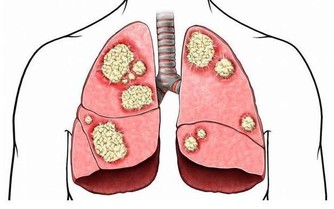

養血管等於養命,血管年輕人不老。但是什麼很多人都出現血管提前老化的現象,年紀輕輕就出現高血脂、血栓。如果血管垃圾不及時清理,就會引發中風、腦出血等高位疾病。所以養血管,從年輕就要開始了!